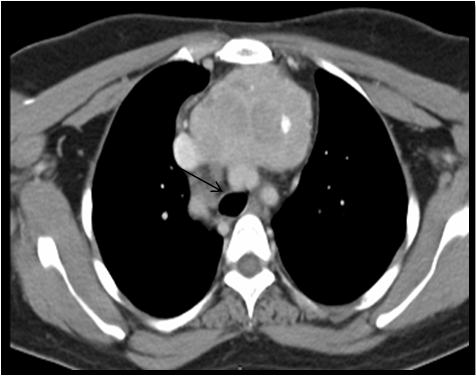

USG neck and CECT scan in view of retrosternal extension, revealed minimum extension of 8cm to maximum of 10cm. All retrosternal extension were descending to the anterior mediastinum, just abutting the level of aortic arch. The mass was causing mild tracheal luminal compromise in 03 cases and in the postero inferior aspect, the lesion was indenting and slightly displacing the aortic arch in 02 cases; however, the intervening fat planes were maintained. Laterally, the lesion was causing indentation of bilateral Internal Jugular Vein in all cases, 03 on right and 02 on left. Rest of the great vessels were normally visualised (Figure 3A, 3B & 3C).

Figure 3C CT image: Axial section at the level of T2-T3 showing retrosternal extension of goitre upto the aortic arch (arrow).